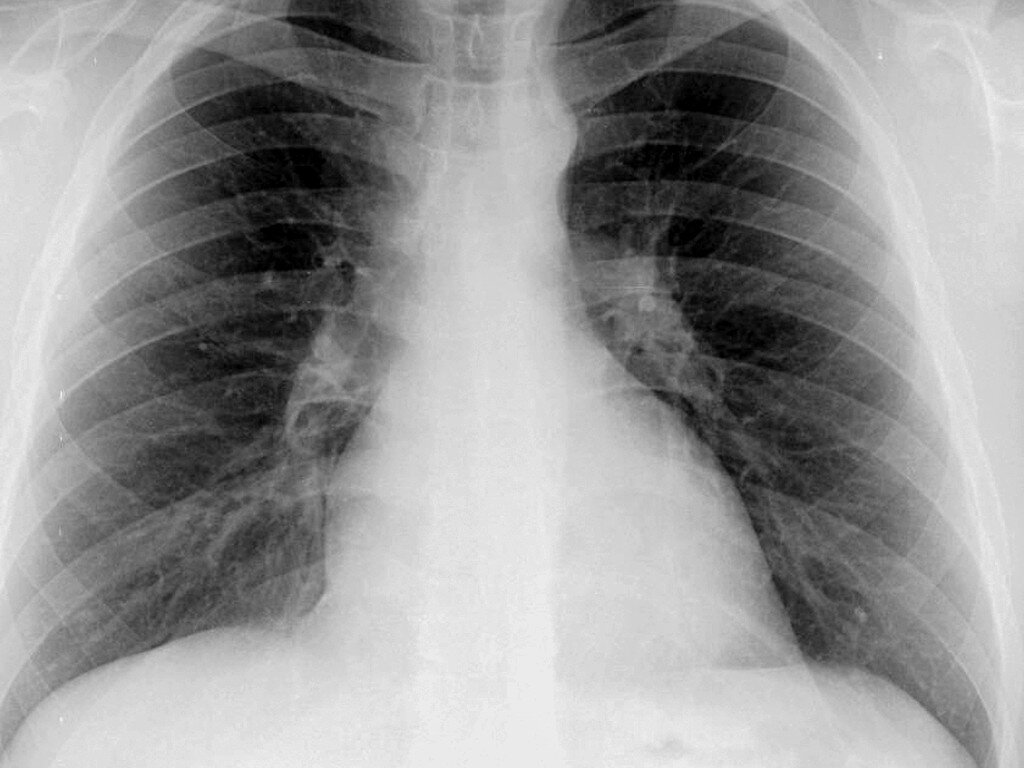

В тот день Господь был благосклонен, наверное, больше к ребёнку, чем к нам, и через два часа девочка начала двигать пальчиками. Я неспеша вернул ребенку из контура остатки её крови, отключил насос и отсоединил магистрали. Колпак и маска у меня были мокрые от пота. Я устало стащил с рук перчатки и обратился к работавшей со мною бригаде: "Спасибо, мои дорогие! Мы сделали это. А теперь лично я - курить". В это время в кабинет принесли рентгенограмму лёгких пациентки. Жадно вдыхая сигаретный дым, мы с Андрюхой уставились на включенный негатоскоп. "Слушай, Михалыч, а ведь нет никаких признаков аспирации - абсолютно чистые легкие. Значит, хорошо и вовремя очистили дыхательные пути" - заключил я...

Это - нормальная рентгенограмма лёгких у ребёнка... Яндекс-фото